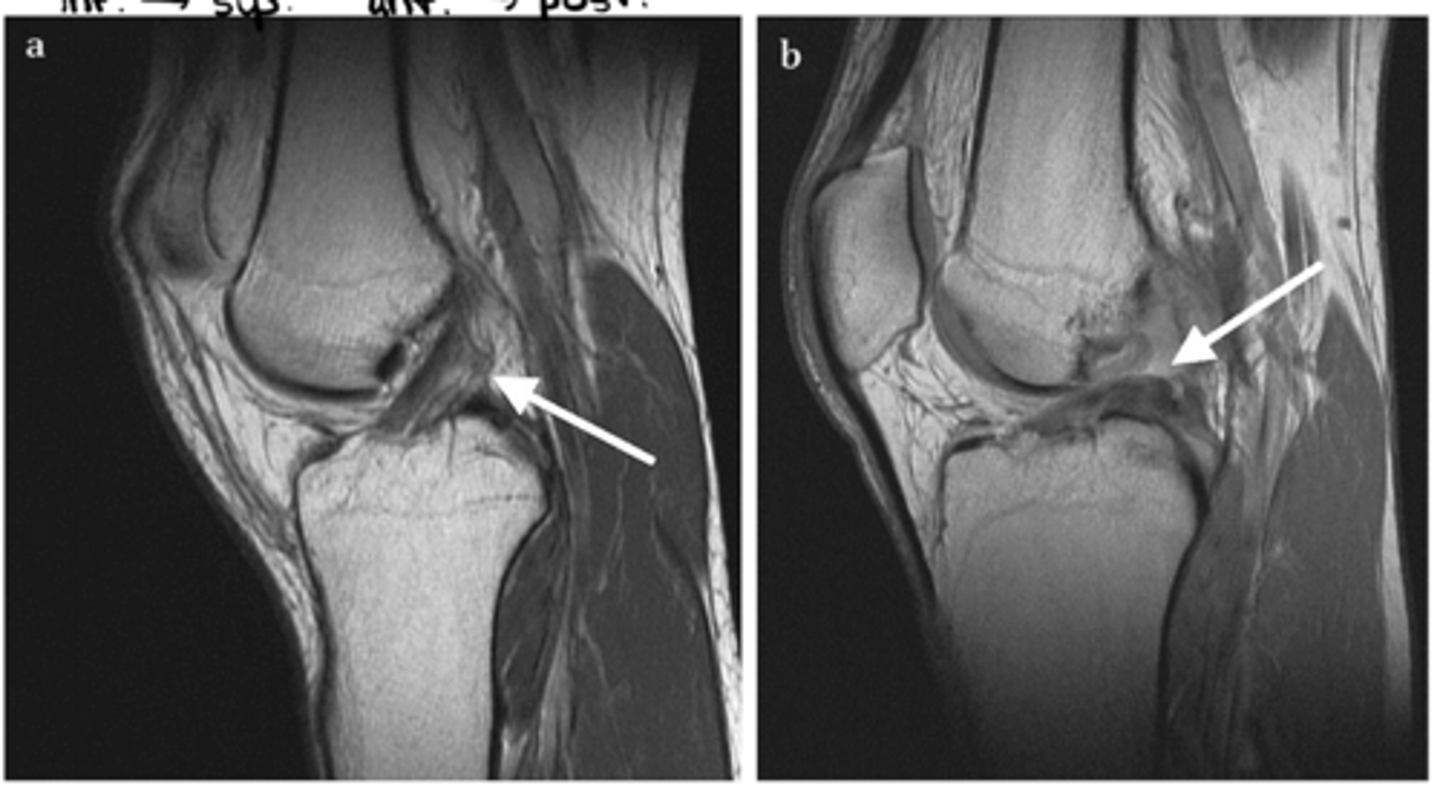

A = healthy ACL running inferior & anterior to superior & posterior

B = fully torn ACL (since the ligament is laying down flat on the tibia, we know that it is a full tear...if it were a partial tear, it would just appear wavy)

What is the difference between image a and b?